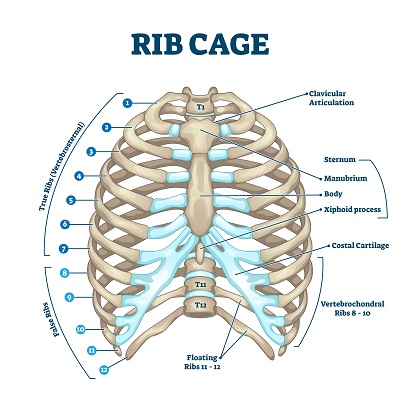

A broken rib typically causes sharp pain. To diagnose a rib injury, it’s best to see a medical professional who can look at your injuries with professional tools and technology. You may also feel or hear a crack or pop when the.

Sometimes, you may be able to feel a break in your rib by rubbing your finger over the rib. If you have a tender area on your ribs that hurts with every breath, you may have a broken rib. If you heard cracking during the injury or you hear or feel cracking when you move or.

Take slow, deep breaths and cough regularly to expand your lungs, use an incentive spirometer if asked to do so, get up and move around when you’re not sleeping,. When visiting your doctor, they will most likely be able to diagnose your injury simply by pushing on your chest and doing a physical exam. The pain you feel with a broken rib typically occurs or even worsens when you: